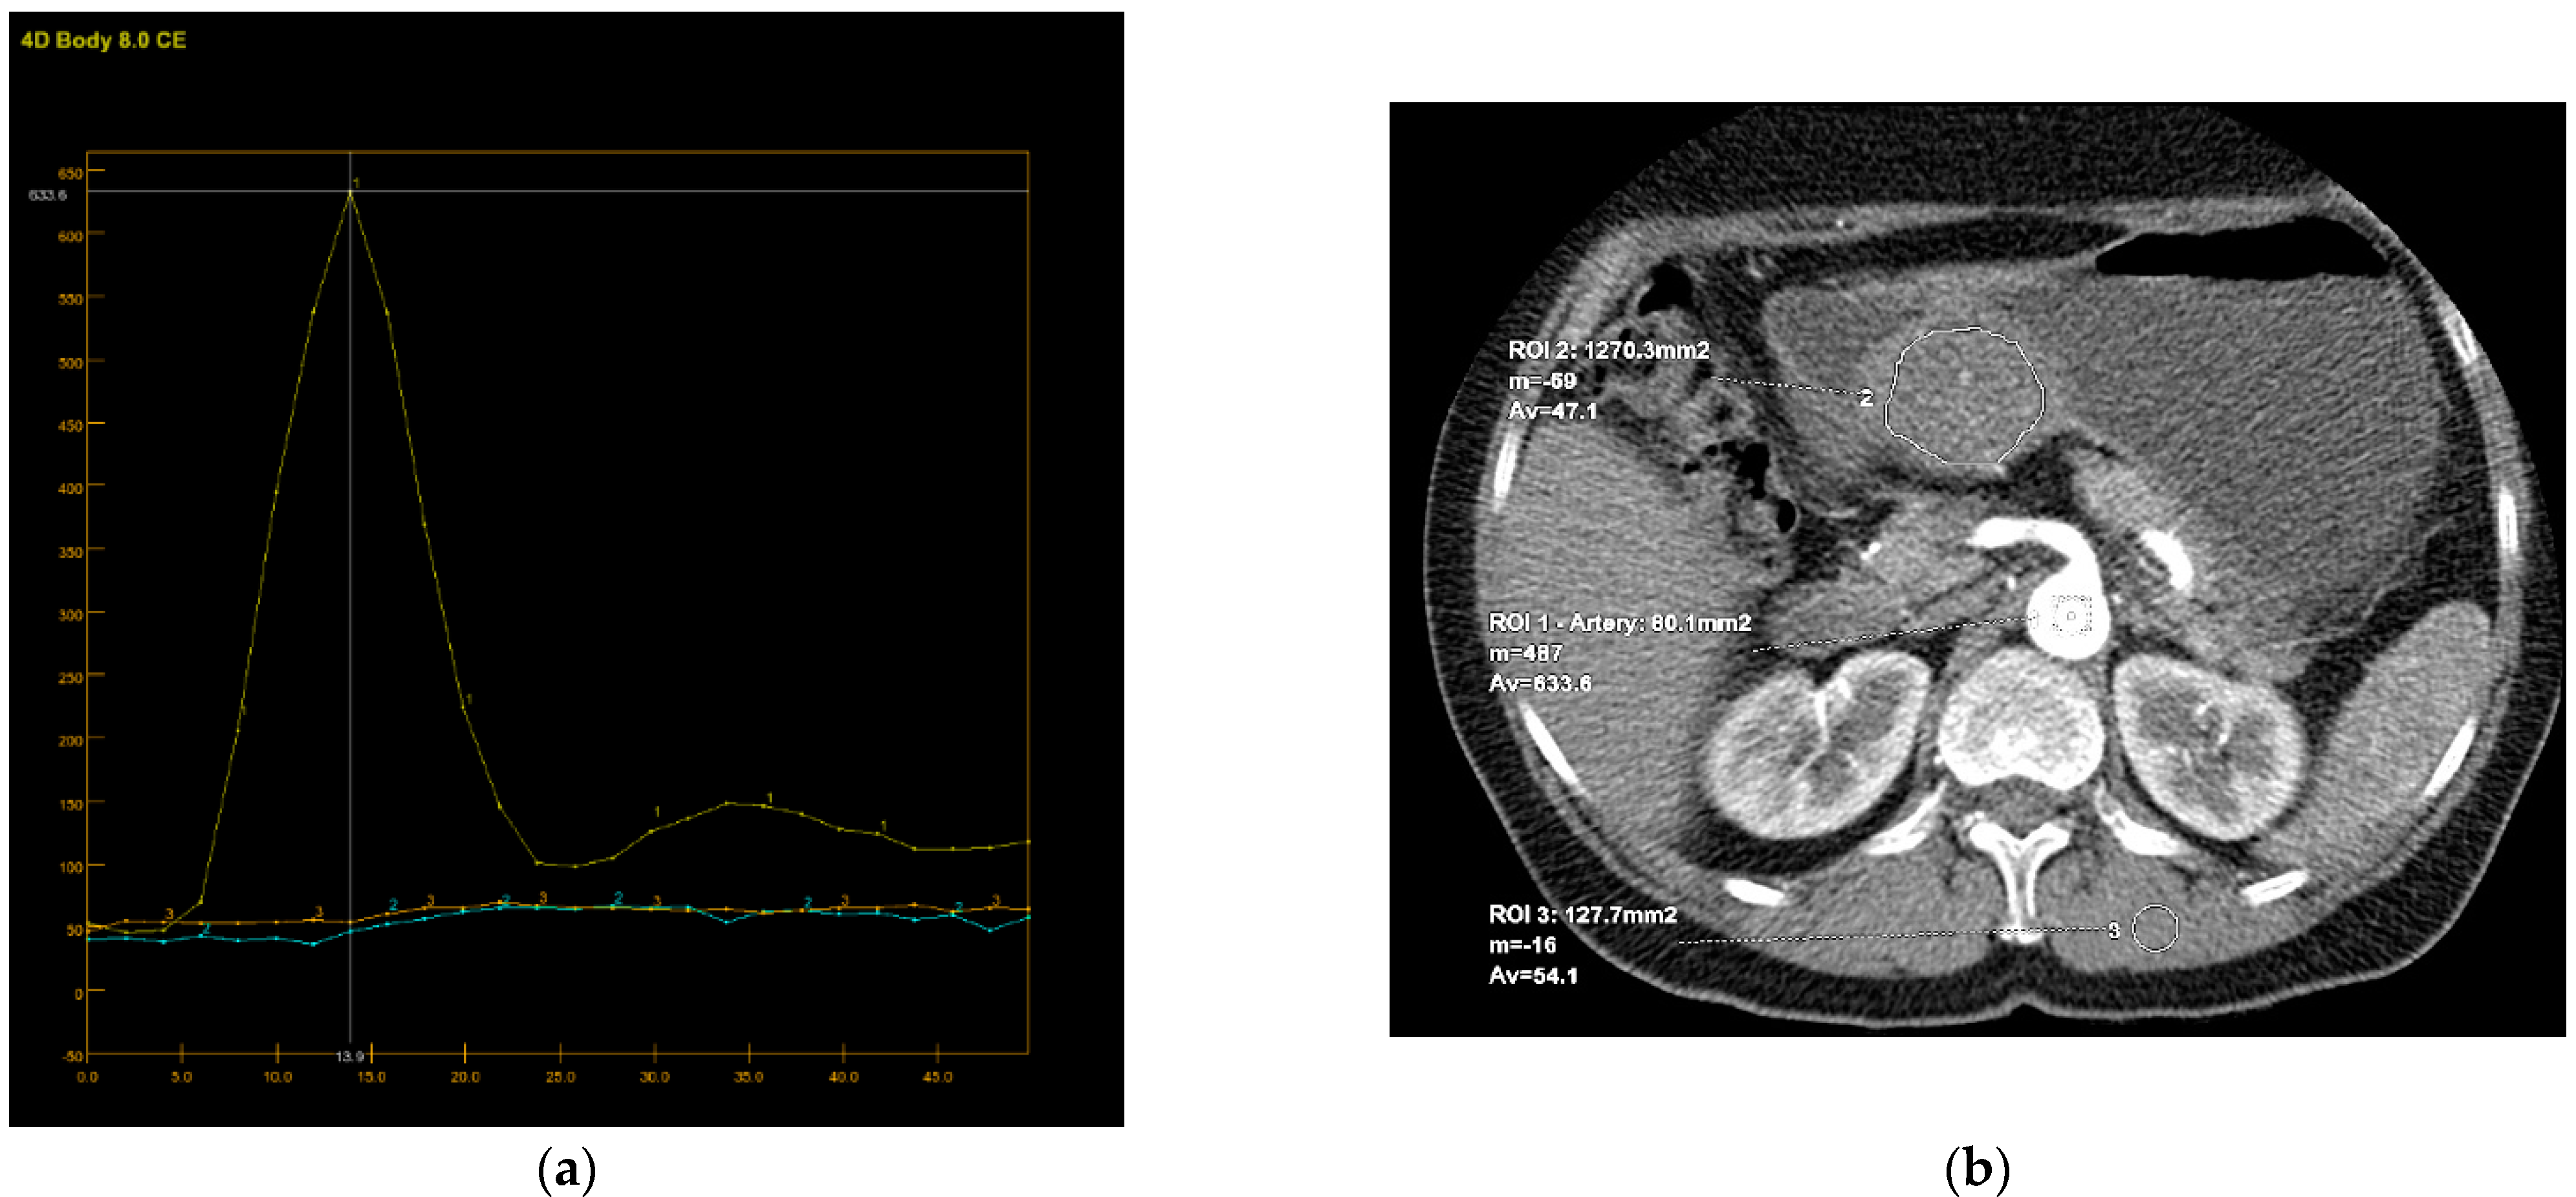

Perfusion CT data were analyzed by calculating perfusion according to the deconvolution method. The arterial input function was obtained from a 4–6 mm² circular region of interest (ROI) that was placed in the abdominal aorta. The arterial time-attenuation curve was derived automatically, and parametric colored maps were displayed for each of the four consecutive series of perfusion CT (Figure 4a). One radiologist placed a circular ROI as large as possible within the solid tumor region as well as in the nearby paravertebral skeletal muscles, taking care to avoid large vessels, at the reference and parametric images on each of the four consecutive slices (Figure 4b).

Figure 4.

An 8-mm reconstructed image from the low-dose CT perfusion series of a 57-years old female patient with gastric GIST. Time-density curve on computed tomography perfusion (a). The arterial (yellow), tumor (blue), and muscle (orange), time-attenuation curves of the corresponding CT perfusion section. A freehand ROI (this tool measures area in square milimeters) in the region of tumor and round ROIs in the aorta and paravertebral muscle (b).

Color parametric maps of the following quantitative perfusion parameters have been automatically computed within these ROIs using the commercial software (Body Perfusion 4.0, GE Health-Care Technologies, USA): blood flow—BF (mL/min/100 g tissue); blood volume—BV (mL/100 g tissue); mean transit time—MTT (s); permeability surface area product—PS (mL/min/100 g tissue); and time to peak—TTP (s) (Figure 5). The values of the perfusion parameters of tumor were recorded for each section of gastric tumor ROI, and the same was done for muscle ROIs. Mean values of the perfusion parameters derived from the four consecutive sections were averaged and used for further analysis.